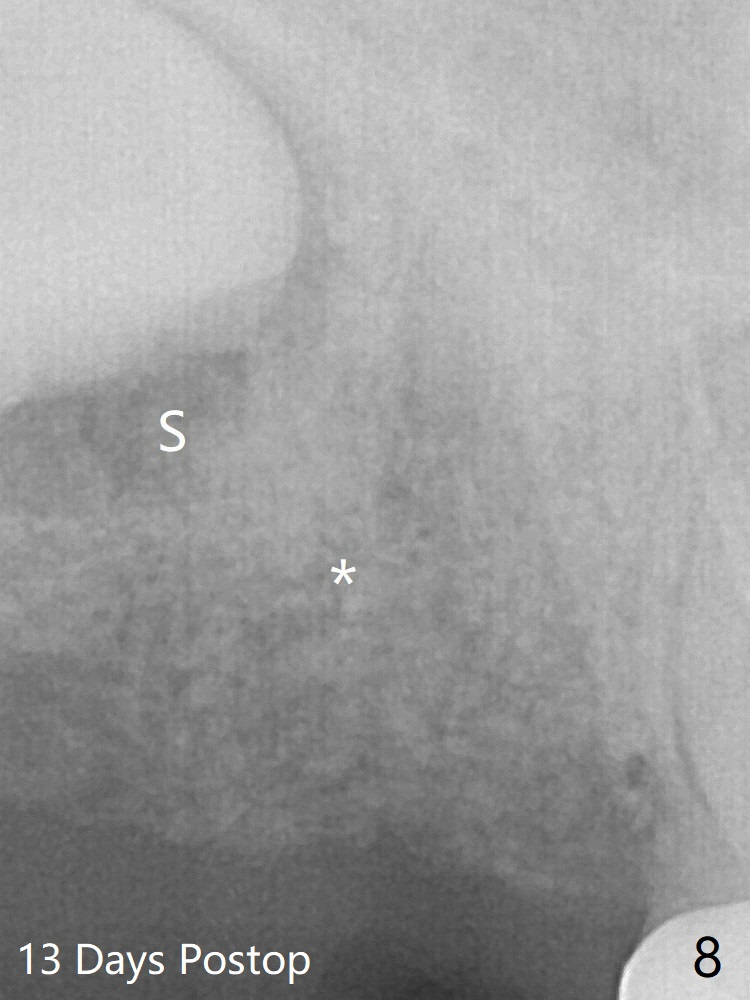

The pattern of bone graft granules changes in 4 months (compare Fig.8,10).